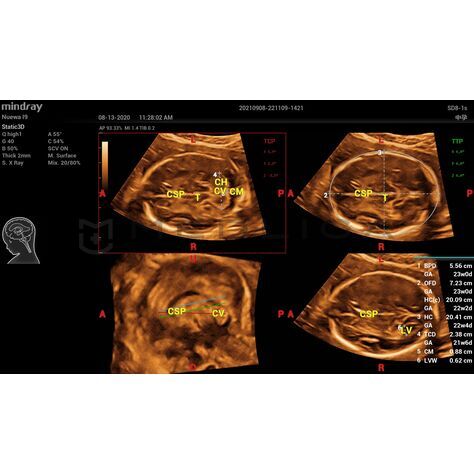

• Полностью автоматическое распознавание срезов, 4 стандартных среза ЦНС

• MSP — интеллектуальная медиальная сагиттальная плоскость

• TCP — трансцеребральная плоскость

• TTP — трансталамическая плоскость

• TVP — трансвентрикулярная плоскость

• BPD — обмер и вычисление бипариентального размера головы

• HC — окружность головы

• OFD — лобно-затылочный размер головы

• TCD — межполушарный размер мозжечка

• CM — ширина большой цистерны

• LVW — ширина боковых желудочков